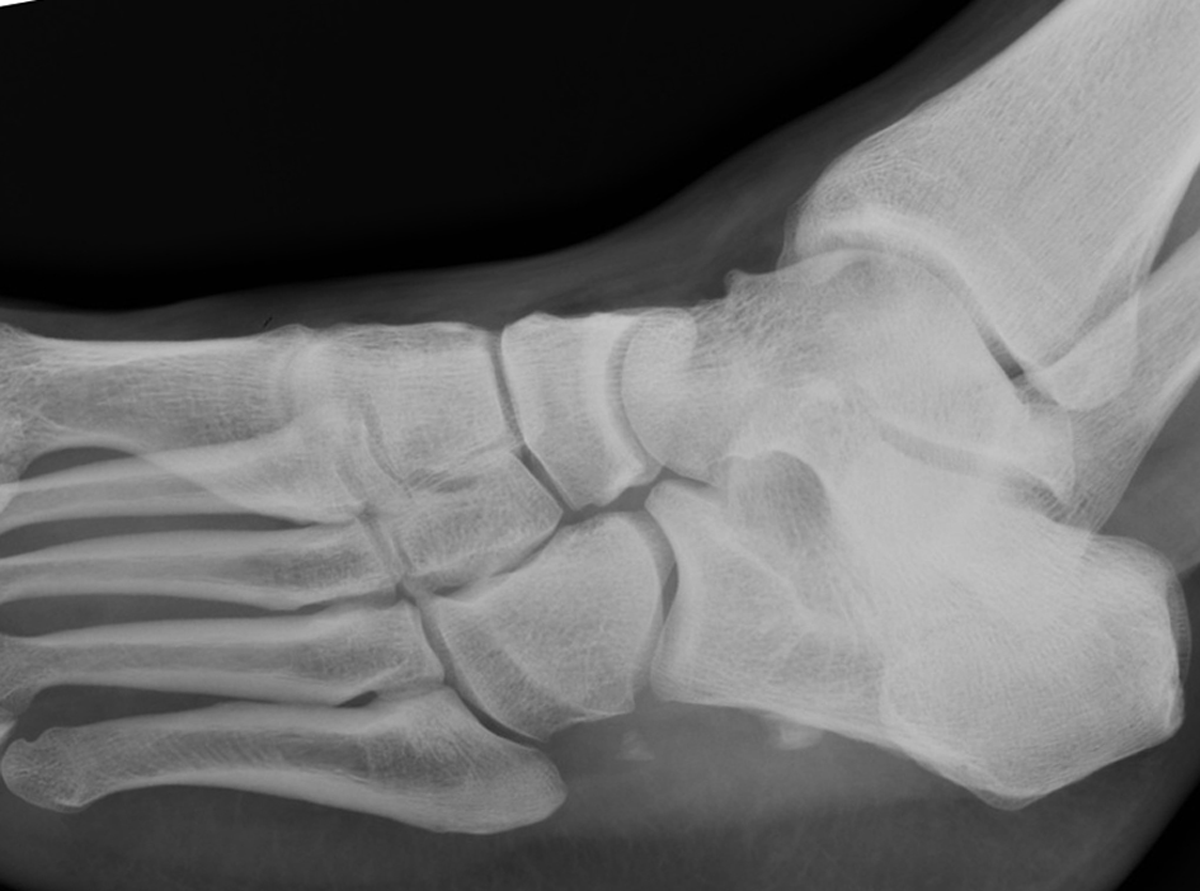

2. Os peroneum fracture

An os peroneum fracture may occur and it invariably indicates an injury to the peroneus longus tendon. In the most severe case, the os peroneum may be retracted beyond the medial malleolus (Figure 1).